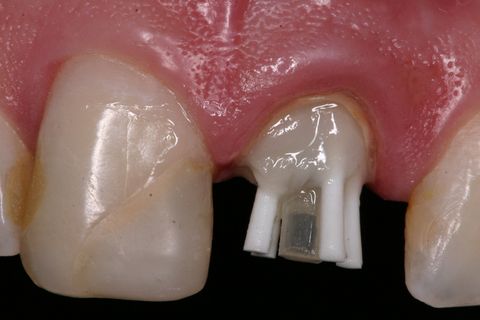

Verificação da adaptação do pino anatômico no remanescente dentário

Aspecto final do pino pós fotopolimerização

Aspecto clínico após cimentação (tempo de 5 min)

Foi realizada uma marcação na porção mais incisal dos pinos para orientar o posterior recorte dos pinos (Figura 12). A seguir, o pino anatômico foi removido e realizado a fotoativação final por 40 segundos (Figura 13). Logo após, verifica-se a adaptação do pino anatômico ao remanescente coronário (Figura 14).

Após a fase de confecção do pino anatômico e porção coronária do núcleo com resina composta, inicia-se a preparação do mesmo para a cimentação adesiva ao remanescente dentário (Figura 15).